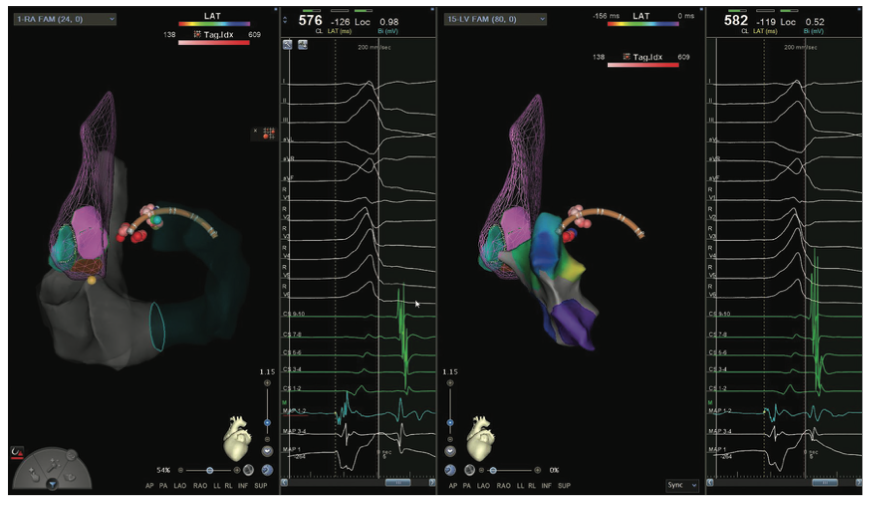

Figures/Videos 1-10 demonstrate the process of navigation from groin access to the heart to create biatrial geometry, localize the esophagus, and gain transseptal access. Many currently practicing electrophysiologists use very little fluoroscopy to map and ablate the left atrium (LA) with the current multielectrode catheters and EAM systems once transseptal access is obtained.

Video 11a and Figure 11b show the voltage map of the LA as well as the pliability of the Pentaray spline catheter to adapt its shape to vessels (a right middle vein) and the endocardium.

Videos 12a-b illustrate the technique for retrograde aortic access without fluoroscopy achieved by merging the ascending aortic sound map with the EAM map created with the catheter as it comes around the arch. The sound map also allows visualization of any plaque that may be present in the aortic root that can be tagged.